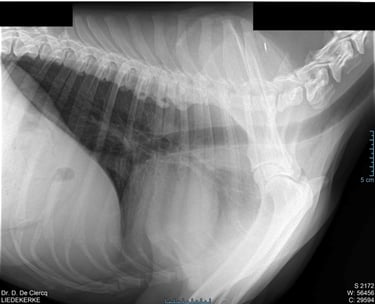

Radiografie (RX)

Consult op de praktijk of aan huis

Een RX is geschikt om botbreuken, een longontsteking, de hartgrootte, arthrose,....op te sporen.

Als de hond - kat niet lang genoeg stil kan blijven liggen dan is een verdoving noodzakelijk. Voor RX van het heupgewricht is een volledige verdoving noodzakelijk.